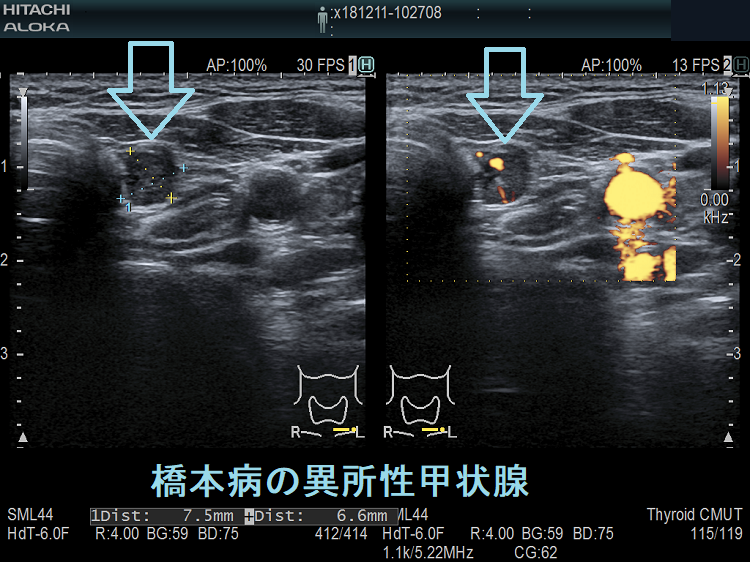

橋本病を合併し、副甲状腺と同じ位置にある頚部異所性甲状腺

橋本病の異所性甲状腺 超音波(エコー)画像

橋本病を合併し、下極の副甲状腺と同じ位置にある異所性甲状腺。甲状腺本体と同様の破壊性変化を認めます。

橋本病の異所性甲状腺 超音波(エコー)画像 ドプラーモード

橋本病を合併した頚部異所性甲状腺:下極の副甲状腺と同じ位置にある異所性甲状腺。特徴的な2連構造で、甲状腺本体と同様の破壊性変化を認めます。